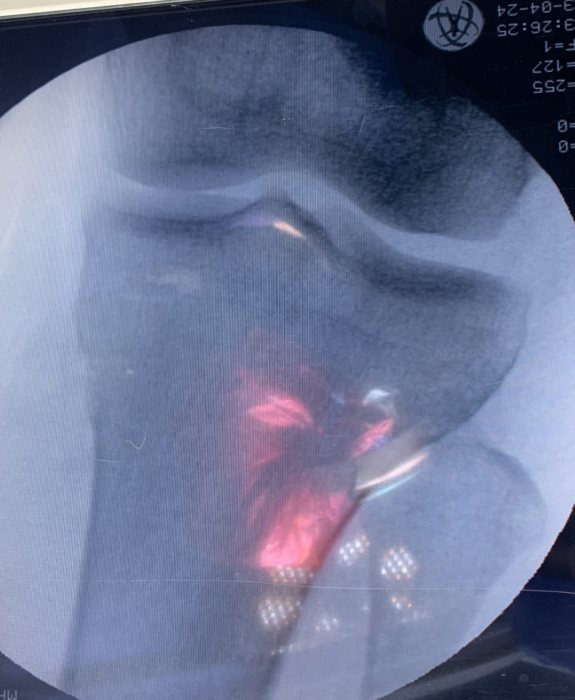

خلال هذه الجراحة، يعيد دكتور العظام و المفاصل استعدال عظام الساق (عظم الساق) أو الفخذ (عظم الفخذ) لإعادة توجيه الركبة. ينقل هذا التوجيه الوزن الجسدي من الجزء المتضرر من ركبتك إلى جزء صحي.

خلال جراحة توسيع الفجوة، يقوم الجراح بقطع قطعة من العظم من الساق ويقرب جوانب الفتحة لإغلاق المسافة.

في بعض الحالات، يفتح الجراح قسمًا من العظم بدلاً من إغلاقه. يُسمى هذا الإجراء شق توسيع الفجوة. في بعض الأحيان يتم استخدام رقعة عظمية وشريحة و مسامير للمحافظة على المسافة بين أطراف الفجوة التي تم توسيعها.

يوجد العديد من الخيارات لتثبيت على الشق العظمي و توسيع الركبة في مكانه حتي تمام الالتئام ، و يمكنك مناقشة هذه الاختيارات مع دكتور العظام المتخصص في الركبة. يتضمن ذلك مسامير معدنية شريحة أو رقعة عظمية للحفاظ على العظام في مكانه أثناء الشفاء. عادة ما تستغرق جراحة توسيع الركبة ساعة إلى ساعتين.